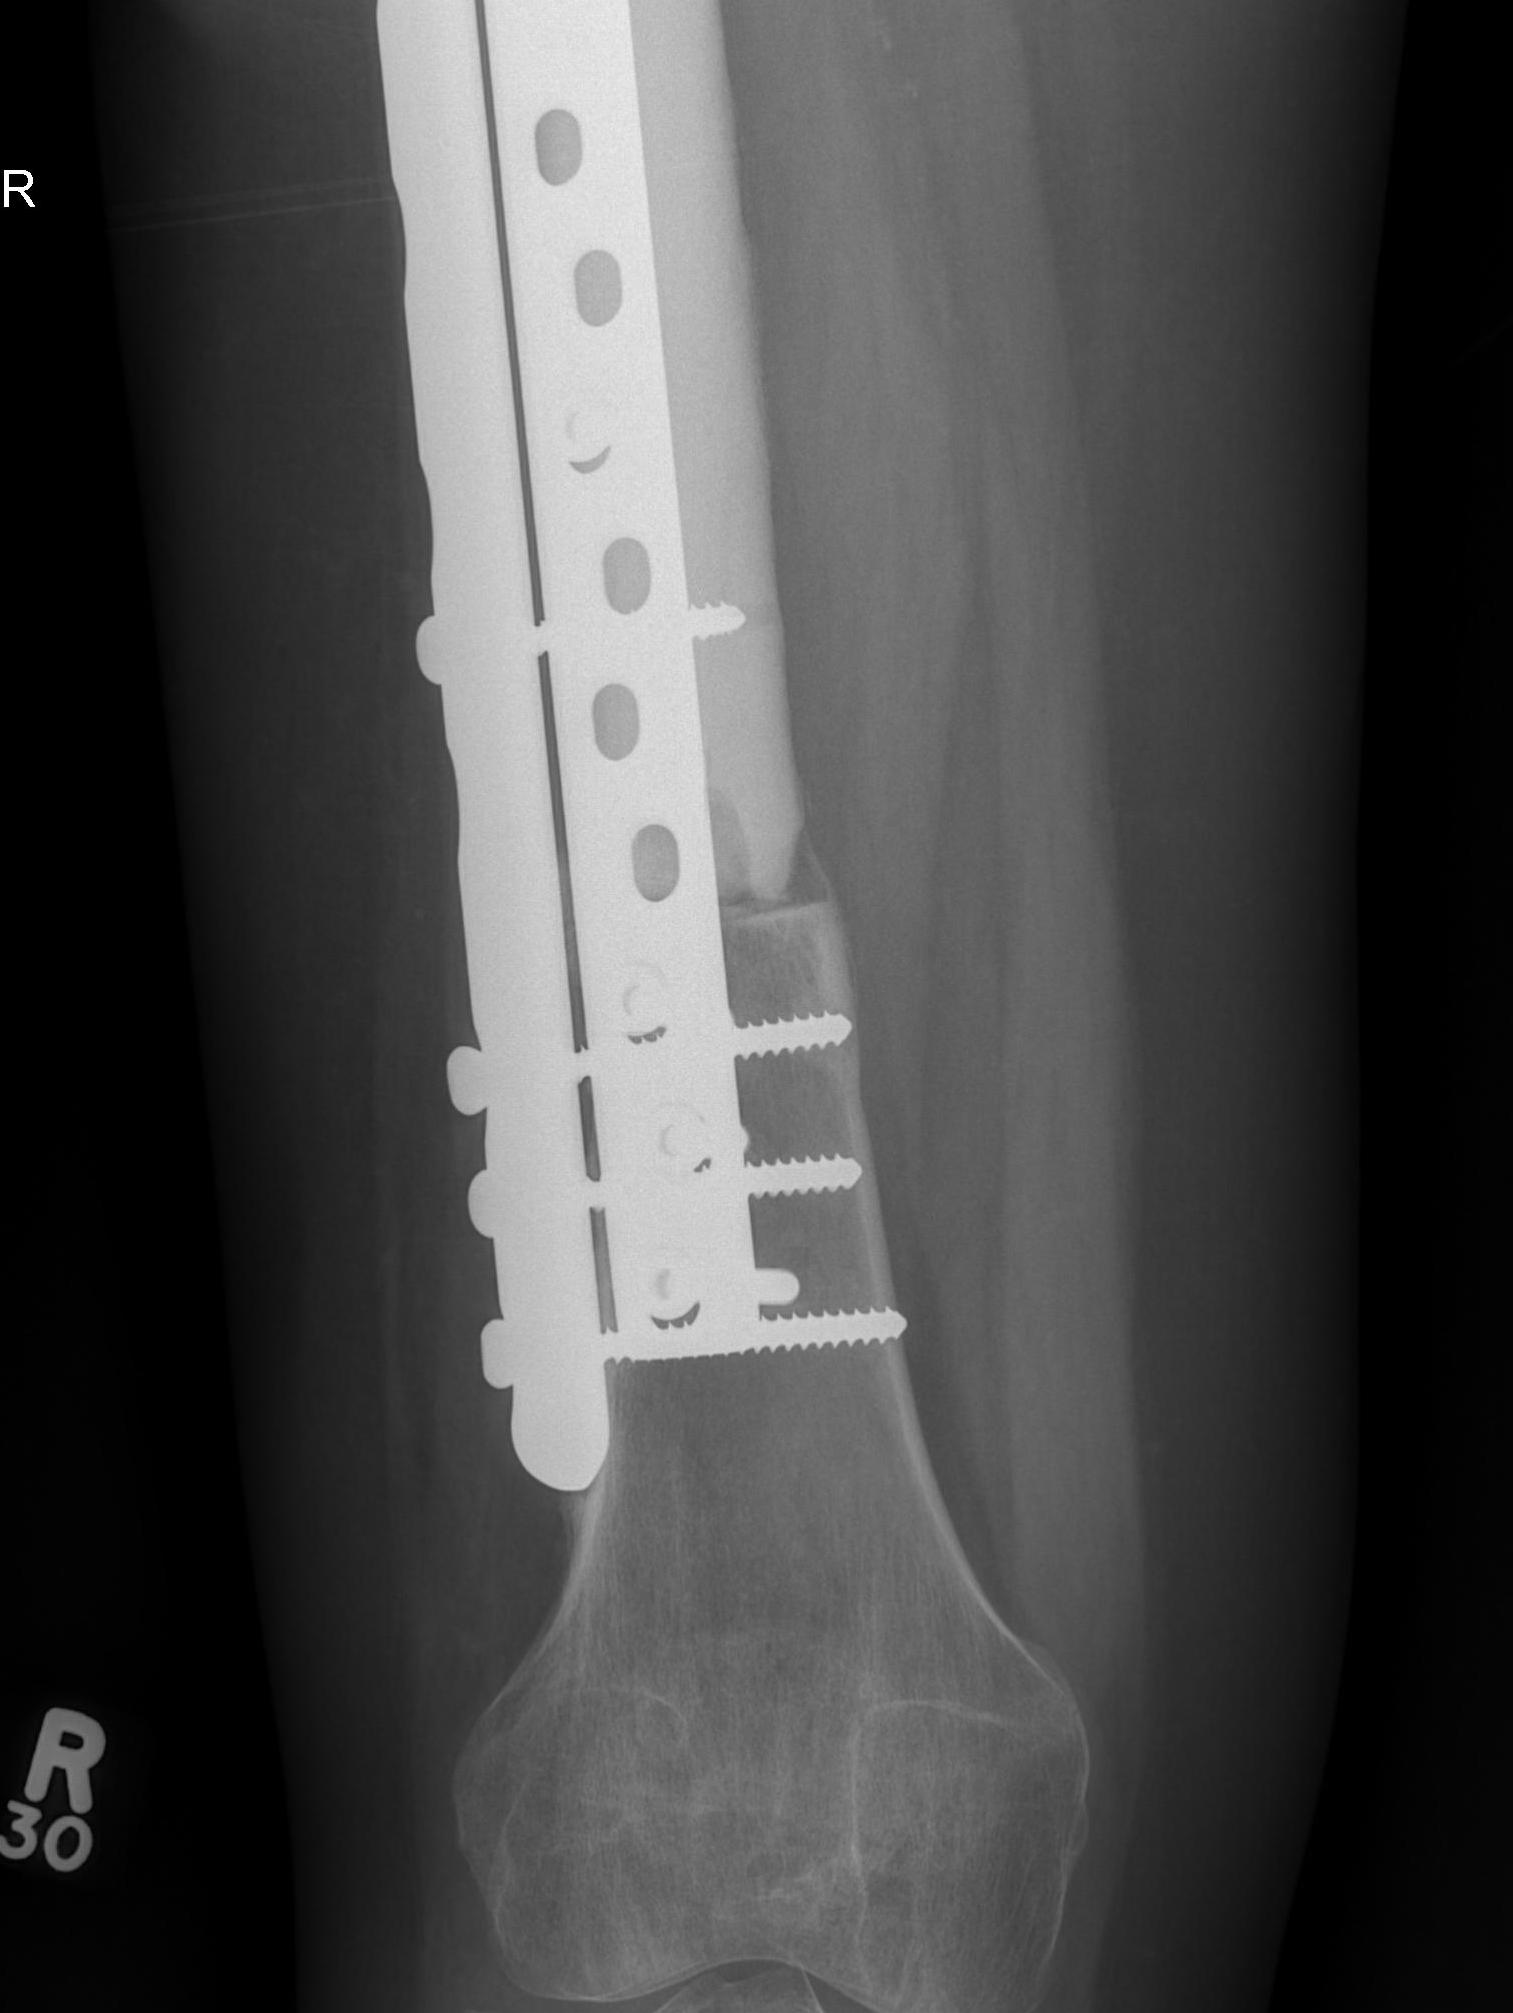

Modular Endoprosthesis

Advantage

Early weight bear and rehabilitation

No risk of non union like allograft

Massive Allograft

- biological reconstruction

- intercalary

- osteochondral

Autograft / Vascularised fibula graft

Advantage over allografts

- more rapid incorporation

- stronger initial construct secondary to graft hypertrophy